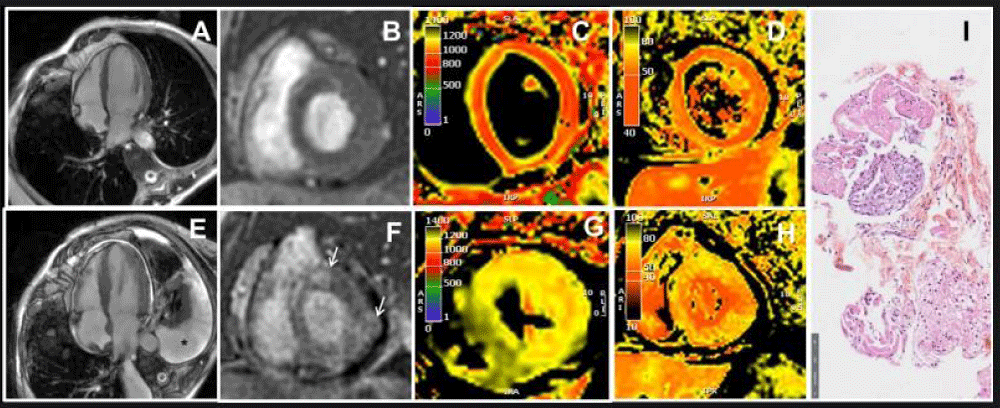

Figure 1: Trans-thoracic echocardiography findings in March 2023 (A, B, C) and in May 2023 (D, E, F).

A-B: Parasternal long-axis and four-chamber echocardiographic view demonstrating normal left ventricular wall thickness.

C: Global longitudinal strain normal at -19.9%.

D-E: Parasternal long-axis and four-chamber echocardiographic view demonstrating increased left ventricular wall thickness.

F: Global longitudinal strain decreased at -9.8%

In December 2022, an initial cardiac workup, including EKG and transthoracic echocardiography (TTE), showed no structural heart disease (LVEF 66%, mean global longitudinal strain (GLS) -19.9%) (Figure 1 A-C). Cardiac biomarkers (troponin and NT-pro-BNP) were within normal limits. By March 2023, during a routine medical follow-up, the patient, who remained asymptomatic, had troponin levels twice the normal range without concurrent elevation in CK. Liver function tests and TSH were within normal range. Follow-up EKG and TTE remained unremarkable.

In late May 2023, the patient was admitted to the cardiac intensive care unit due to quickly worsening dyspnea. Her NT-pro-BNP level had significantly increased to 4300 pg/mL, and her troponin level was three times the normal limit. She exhibited severe hyperlactatemia at 6 mmol/L. This hyperlactatemia remained stable, plateauing around 5-6 mmol/L, despite the initial absence of other signs of peripheral hypoperfusion for several days. On EKG, first-degree atrioventricular block and incomplete right bundle branch block were observed. TTE revealed left ventricular hypertrophy with a hyper-echogenic myocardium. While the left ventricular ejection fraction was normal (62%), the global longitudinal strain was altered with apical sparing (GLS = -9.8%). The right ventricle wall was also thickened and there was a pericardial effusion (Figure 1 D-F). CMR was performed and revealed features of acute myocarditis with diffuse myocardial edema and the presence of late gadolinium enhancement predominantly in the lateral wall, forming a very nodular shape (Figure 2 E-H). There was also a widespread and significant increase in extracellular volume between 45% and 50%. A pericardial effusion and right ventricle hypertrophy were also present. Left ventricular ejection fraction was preserved (69%). An abdominopelvic computed tomography scan performed due to hyperlactatemia revealed a heterogeneously enlarged liver and spleen with multiple secondary lesions, extensive intraperitoneal effusion, and mesenteric infiltration which could explain the hyperlactatemia.